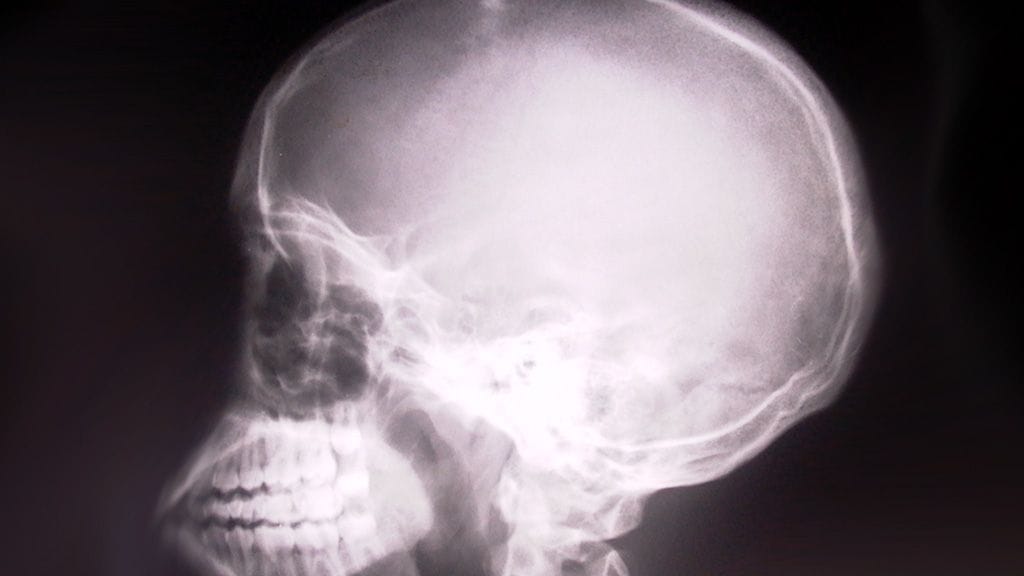

Intiassa lääkärit ovat poistaneet 1,8 kilon painoisen aivokasvaimen 31-vuotiaalta mieheltä. Lääkärit arvelevat, että kyseinen kasvain saattaa olla maailman suurin.

BBC kertoo, että operaatio tehtiin Mumbaissa ja se kesti seitsemän tuntia. Mies on parhaillaan toipumassa leikkauksesta.

Mies oli joutunut elämään valtavan kasvaimen kanssa kolme vuotta ennen leikkausta. Hän oli menettänyt näkönsä kasvaimen takia, mutta lääkärit toivovat näön palaavan toipumisen myötä.